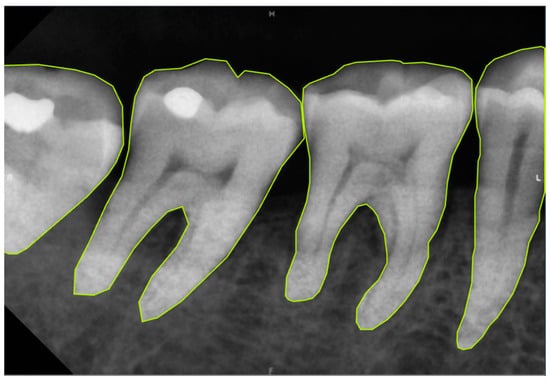

The prediction results of the three masks (Tooth, Bone, and Crown) using the aforementioned steps are shown in Figure 12, with different AP metrics evaluated using Equation (8). Table 9 presents the training results of Mask R-CNN for extracting these masks from original and enhanced images, assessed through AP, AP50, and AP75 metrics. For the Tooth Mask, image enhancement improved the AP from 66.73% to 69.65%, AP50 from 88.32% to 89.54%, and AP75 from 74.65% to 81.66%. For the Bone Mask, the AP increased from 73.32% to 76.66%, AP50 from 98.15% to 99.86%, and AP75 from 90.17% to 92.26%. For the Crown Mask, the AP improved from 79.14% to 81.55%, AP50 remained at 99.99%, and AP75 slightly decreased from 98.02% to 96.29%. These results indicate that whether using the bounding box or segmentation evaluation methods, the training outcomes for all three masks improved after image enhancement. This demonstrates the significant effectiveness of image enhancement techniques in increasing the detection accuracy of the Mask R-CNN model. The training process is shown in Table 10. The accuracy of Faster R-CNN for bounding box prediction and Mask R-CNN for mask segmentation prediction has significantly increased to more than 95% during the training process.

Figure 12.

Mask R-CNN prediction result: (a) single tooth (CLAHE), (b) Tooth Mask, (c) Bone Mask, and (d) Crown Mask.